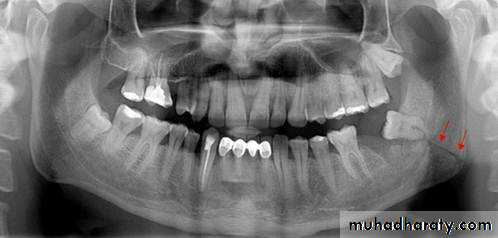

7- Impacted teeth :

Retention of unerupted teeth beyond the normal time of eruption may sometimes be responsible for :

a) Vague facial pain .

b) Periodontal problem of the adjoining teeth .

c) Temporomandibular joint problems .

d) Bony pathology e.g. cyst (dentisgerous cyst ) , tumor pathologically fracture .

e) May predispose to anterior teeth crowdening .

f) Significant infection (pericornoitis) e.g. partially erupted third molar .